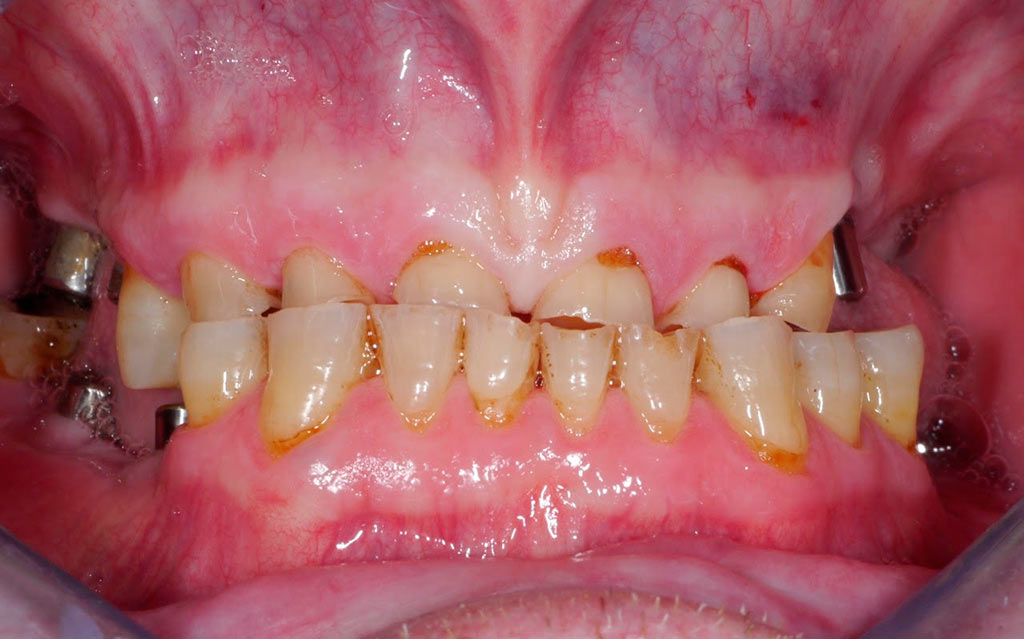

Rehabilitacion de paciente con destrucción dental